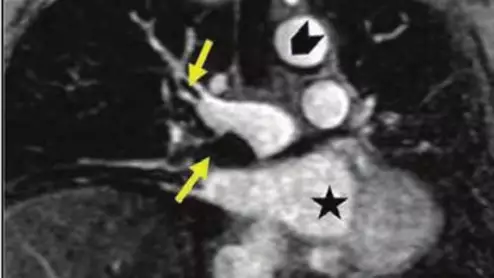

MRA for pulmonary embolus

The modality switch became especially important during the iodinated contrast shortage of 2022 when clinics were forced to deploy mitigation tactics as a means of preserving their contrast supply.